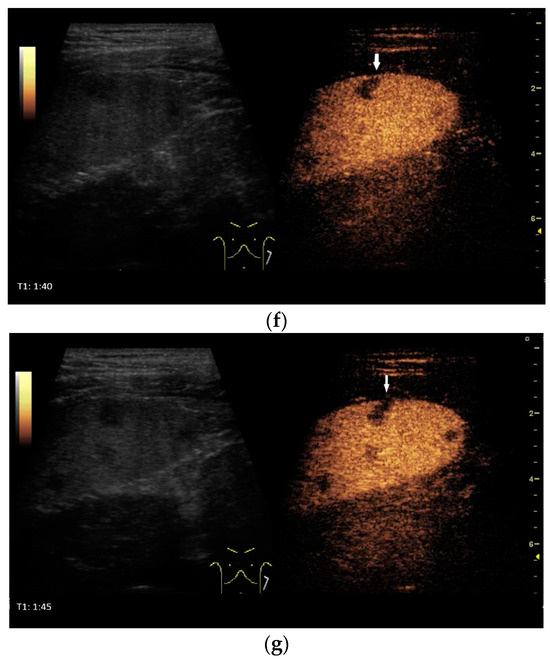

Spleen involvement usually only occurs in disseminated disease. The manifestations are splenomegaly, hypoechoic micronodular (miliary), or macronodular lesions [8,74], as well as splenic abscesses [75] [Figure 4a–d]. In a group of patients with tuberculosis and mostly advanced HIV infection, 37% had splenic lesions [5]. In 33%, splenic lesions were associated with lymphadenopathy, and 16% each had splenic lesions and ascites or splenic lesions, ascites, and lymphadenopathy. Micronodular lesions may be indistinguishable. If this is suspected, examination with a high-resolution linear transducer is recommended. Using CEUS, splenic lesions in the arterial phase showed a hyperenhancement, followed by either a slow washout or a persistent enhancement in the middle and late parenchymal phase [76]. A fast washout was the exception, but nevertheless was also possible. These exceptional cases would therefore be difficult to differentiate from malignancies. There was also rim-like enhancement with central nonenhancement, like abscesses and septation-like enhancement [76]. Another study using CEUS in splenic manifestations of tuberculosis presented homogeneous enhancement (6.7%), heterogeneous enhancement (63.3%), and nonenhancement (30.0%). Most of the cases showed low enhancement. Among these cases, heterogeneous enhancement was divided into septal enhancement type (21.1%) and marginal enhancement type (78.9%) [77] [Figure 4c–g]. The most important differential diagnoses are non-Hodgkin’s lymphoma and other granulomatous inflammations, such as sarcoidosis, especially in the presence of lymphadenopathy. The splenic lesions must be differentiated from mycotic abscesses, leukemic infiltrates, and metastases. In the meta-analysis conducted by van Hoving et al. [78], splenic lesions as manifestations of abdominal tuberculosis had a broad sensitivity of 13–62% in five studies using B-mode ultrasonography. The specificity was higher, at 86–100%.

Figure 4.

Sonographic and CEUS features of splenic tuberculosis. Sonographic and CEUS features of splenic tuberculosis. Subcapsular splenic lesion (arrow) (a), subcapsular splenic lesion using a linear transducer of 12 MHz (arrows) (b). Histologically confirmed tuberculosis from mediastinal lymph nodes. Multiple small splenic lesions (c). Using CEUS with a linear transducer (9 MHz), these are slightly hypoenhanced in the arterial phase (d), and show a progressive washout in the course of the venous phase (arrows) (e). Subcapsular splenic lesion (arrow) with nonenhanced and hypoenhanced parts and hyperenhanced rims indicate a caseous necrosis (f). In another section, an interrupted spleen capsule (arrow) due to a rupture of the caseous necrosis can be assumed (g).